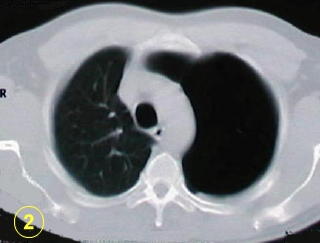

Cuando están infectadas, las imágenes

radiológicas saculares de paredes delgadas y contenido hidro-aereo,

(con niveles líquidos), el diagnóstico diferencial con el

absceso pulmonar esta planteado.

Esta forma de presentación de bula

unica, o localizada en un segmento único, de la enfermedad bulosa

pulmonar no es clásica.

Ocacionalmente es difícil diferenciarla

del neumotórax expontáneo.

La tomografía computarizada del tórax

y su adecuada interpretación es de gran ayuda diagnóstica

en las patologias del tórax.